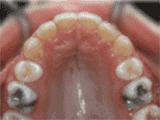

第十种:

深覆盖,咬牙时,上牙差不多完全把下牙挡住了,黄飞鸿的弟子牙擦苏就是这类,经过矫正后的牙齿是这样的~